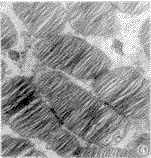

大鼠的光感受器只有视杆细胞。其核区构成视网膜外核层,排列整齐,核染色质分布均匀(图1);内节中具有线粒体等细胞器;外节质膜内褶形成重叠排列的盘状结构即膜盘,结构清晰,排列整齐(图2)。

图1 正常大鼠视杆细胞排列整齐,异染色质分布均匀 CON EM×4000

Fig.1 Rod cells arranging uniformly,chromatin distributing evenly in normal rats CON EM×4000

图2 正常大鼠视杆细胞膜盘排列整齐,结构清晰 CON EM×15000

Fig.2 Membrane disks of rods arranging in good order and their structure being distinct in normal rats CON EM×15000